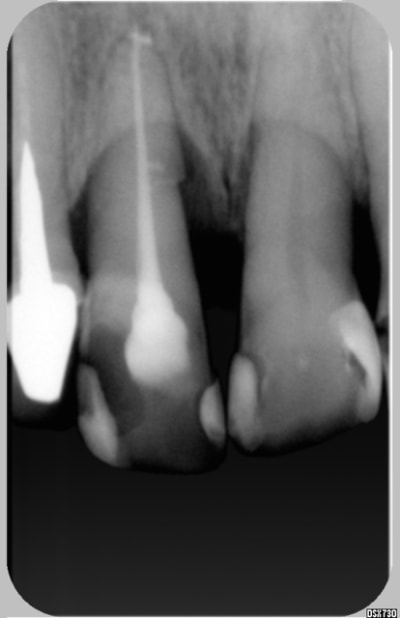

Est ce vraiment unr fracture?

Je vous joint une radio prise en oct 98, la 11 est mobile sans grande sensibilté au froid, suppra profonde.

J'ai soulagé l'occlusion, et surfacage , tout est rentré dans l'ordre

elle revient en 09/2004 apres un épisiode douloureux avec abcés, j'ai éléimine d'emblée un problême paro, et plus de sensibilité

j'ai traité la dent, voir la deuxiéme radio

Un beau canal latéral

depuis génée devant au niveau collet gingival, j'ai du cureté l'exces de pate, la dent n'a plus de mobilité, et les douleurs ont disparues

jeff2 ton cas pour moi c'est pas un canal lateral au depart c'est une felure car sur la derniére image il me semble qu'il y a un decrochement en mesial qui est apparu et qui traduit le deplacement Non???. D'ailleurs le parodonte environnant n'est pas stabilisé.......enfin me semble-t -il

Jeff2, ton cas ne correspond pas au mien regarde bien l'image du canal...

canal lat ou fracture? la derniere radio ne Jeff2 ne m'a pas encore convaincu...mais c'est vrai que l'endo est tres belle...

Revue hier, mobilité, nouvelle radio fracture confirmée mais sensibilité -

Sinon à la radio, j'ai plus l'impression d'une lyse apicale que d'une fracture.